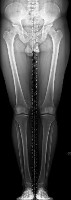

Question 30:

A 2-year-old girl is brought to the pediatric orthopedic clinic by her parents due to worsening bilateral 'bowlegs.' Radiographs reveal a metaphyseal-diaphyseal angle of 18 degrees on the right and 19 degrees on the left, along with medial physeal beaking. She is diagnosed with infantile Blount disease (tibia vara). What is the most appropriate initial management?

Options:

- Observation and reassurance

- Knee-ankle-foot orthoses (KAFOs)

- Proximal tibial valgus osteotomy

- Hemiepiphysiodesis of the lateral proximal tibia

- Guided growth using tension band plates

Correct Answer: Knee-ankle-foot orthoses (KAFOs)

Explanation:

In infantile Blount disease, a metaphyseal-diaphyseal angle (MDA) greater than 16 degrees predicts progression of the deformity, distinguishing it from physiologic bowing. For children under the age of 3 with Langenskiöld Stage I or II and an MDA > 16 degrees, bracing with a knee-ankle-foot orthosis (KAFO) is the recommended initial management. Surgical intervention (osteotomy or guided growth) is indicated if bracing fails, or typically if the child is over 3-4 years old with advanced stages.